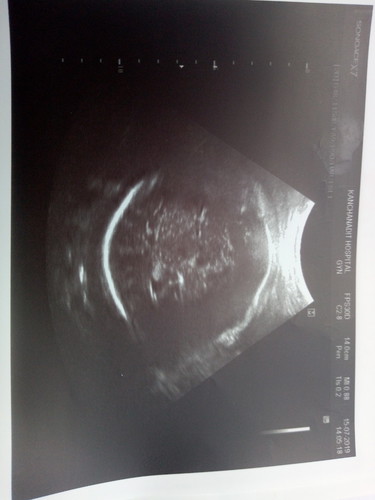

ผลซาววันนี้37w3d

อยากรุ้ได้ผญ.หรือ ผช.ค่า

ดูยากมากค่า